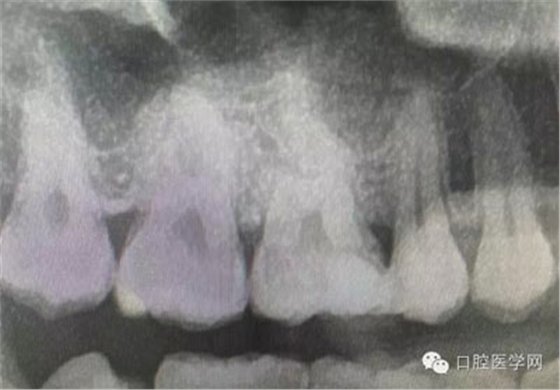

深齲或者是齲壞備洞的時候意外穿髓,我們怎么處理好些?后期出現(xiàn)的牙髓的癥狀,是我們操作的問題?比如細菌層的存在,我們沒有清理干凈?還是我們窩洞沒有進行消毒,或者是隔濕沒有做好導(dǎo)致的粘結(jié)出現(xiàn)問題,還是材料充填的時手法不對,導(dǎo)致的材料收縮過大,還是我們的光照設(shè)備出現(xiàn)了老化沒有完全達到想要的固化,還是懸空的釉質(zhì)沒有去除導(dǎo)致的微滲漏的發(fā)生,或者是材料本身對牙髓產(chǎn)生的刺激,還是材料選擇的問題,或者是我們對材料的性能和說明沒有足夠的了解導(dǎo)致的,沒有按照材料的要求去做,還是我們自身對牙齒情況的判斷出現(xiàn)的問題......

這是一例外院樹脂修復(fù)后十個月出現(xiàn)牙髓炎癥狀的患者。遇到這樣子的患者大家會怎么做,證明選擇,還有就是可做可不做治療的如何去平衡。